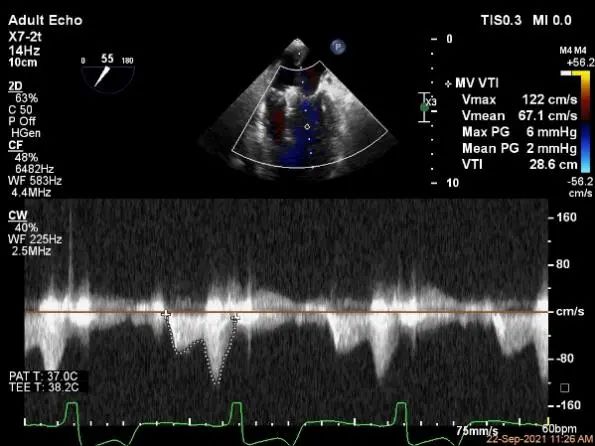

评估瓣口条件,平均跨瓣压差:2mmHg,决定在第一个夹子外侧下第二个夹子

评估瓣口条件,平均跨瓣压差:4mmHg